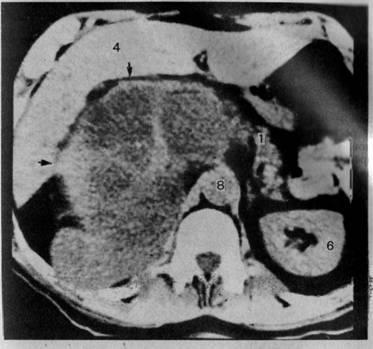

Симптомы и диагностика: Симптомы рака головки поджелудочной железы могут быть неясными и включать желтуху, потерю веса и боли в животе. Это приводит к тому, что заболевание часто выявляется на более поздних стадиях. Использование современных методов визуализации, таких как МРТ и КТ, а также биопсия, может помочь в более ранней диагностике.